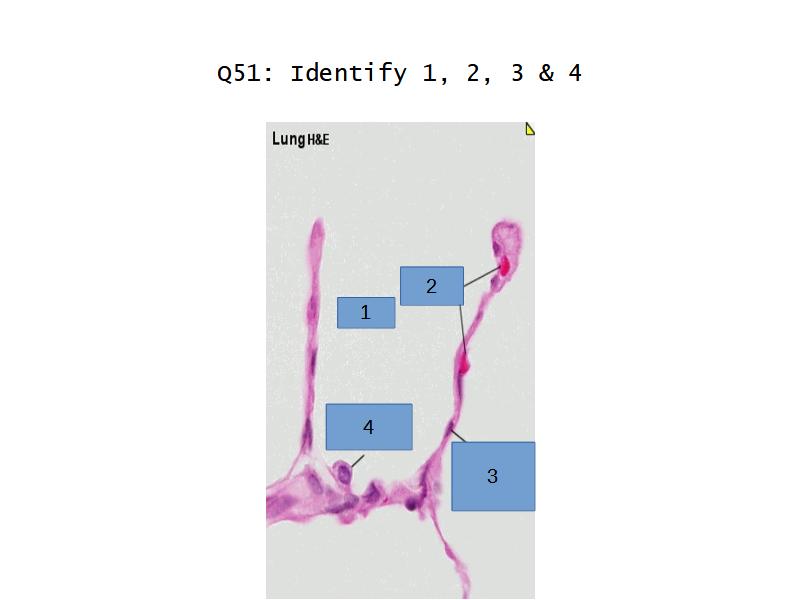

What cells are present?

Components of the Blood-Air Barrier?

- Alveoli

Lungs